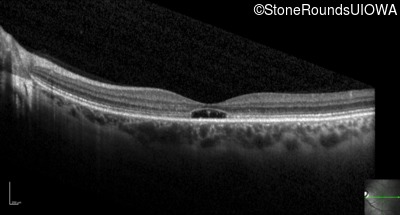

Optical Coherence Tomography - Right - 20/20 -1

Exemplar / OCT Stack